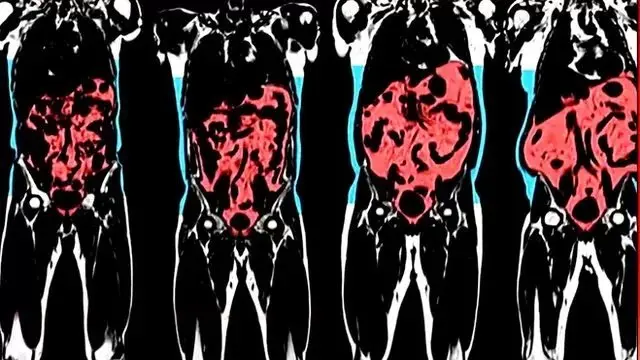

英國最近更新的健康指南鼓勵人們經常檢查一下自己的腰圍,以確保腰部沒有太多的危險脂肪。

腹部脂肪多會增加二型糖尿病、高血壓、心臟病以及中風等風險。

這一方法要比BMI更有助於人們了解自己體內是否堆積過多的內臟脂肪(visceral fat),內臟脂肪通常聚集在心臟、肝臟和胰臟周圍,會增加糖尿病、心臟病和高血壓的風險。